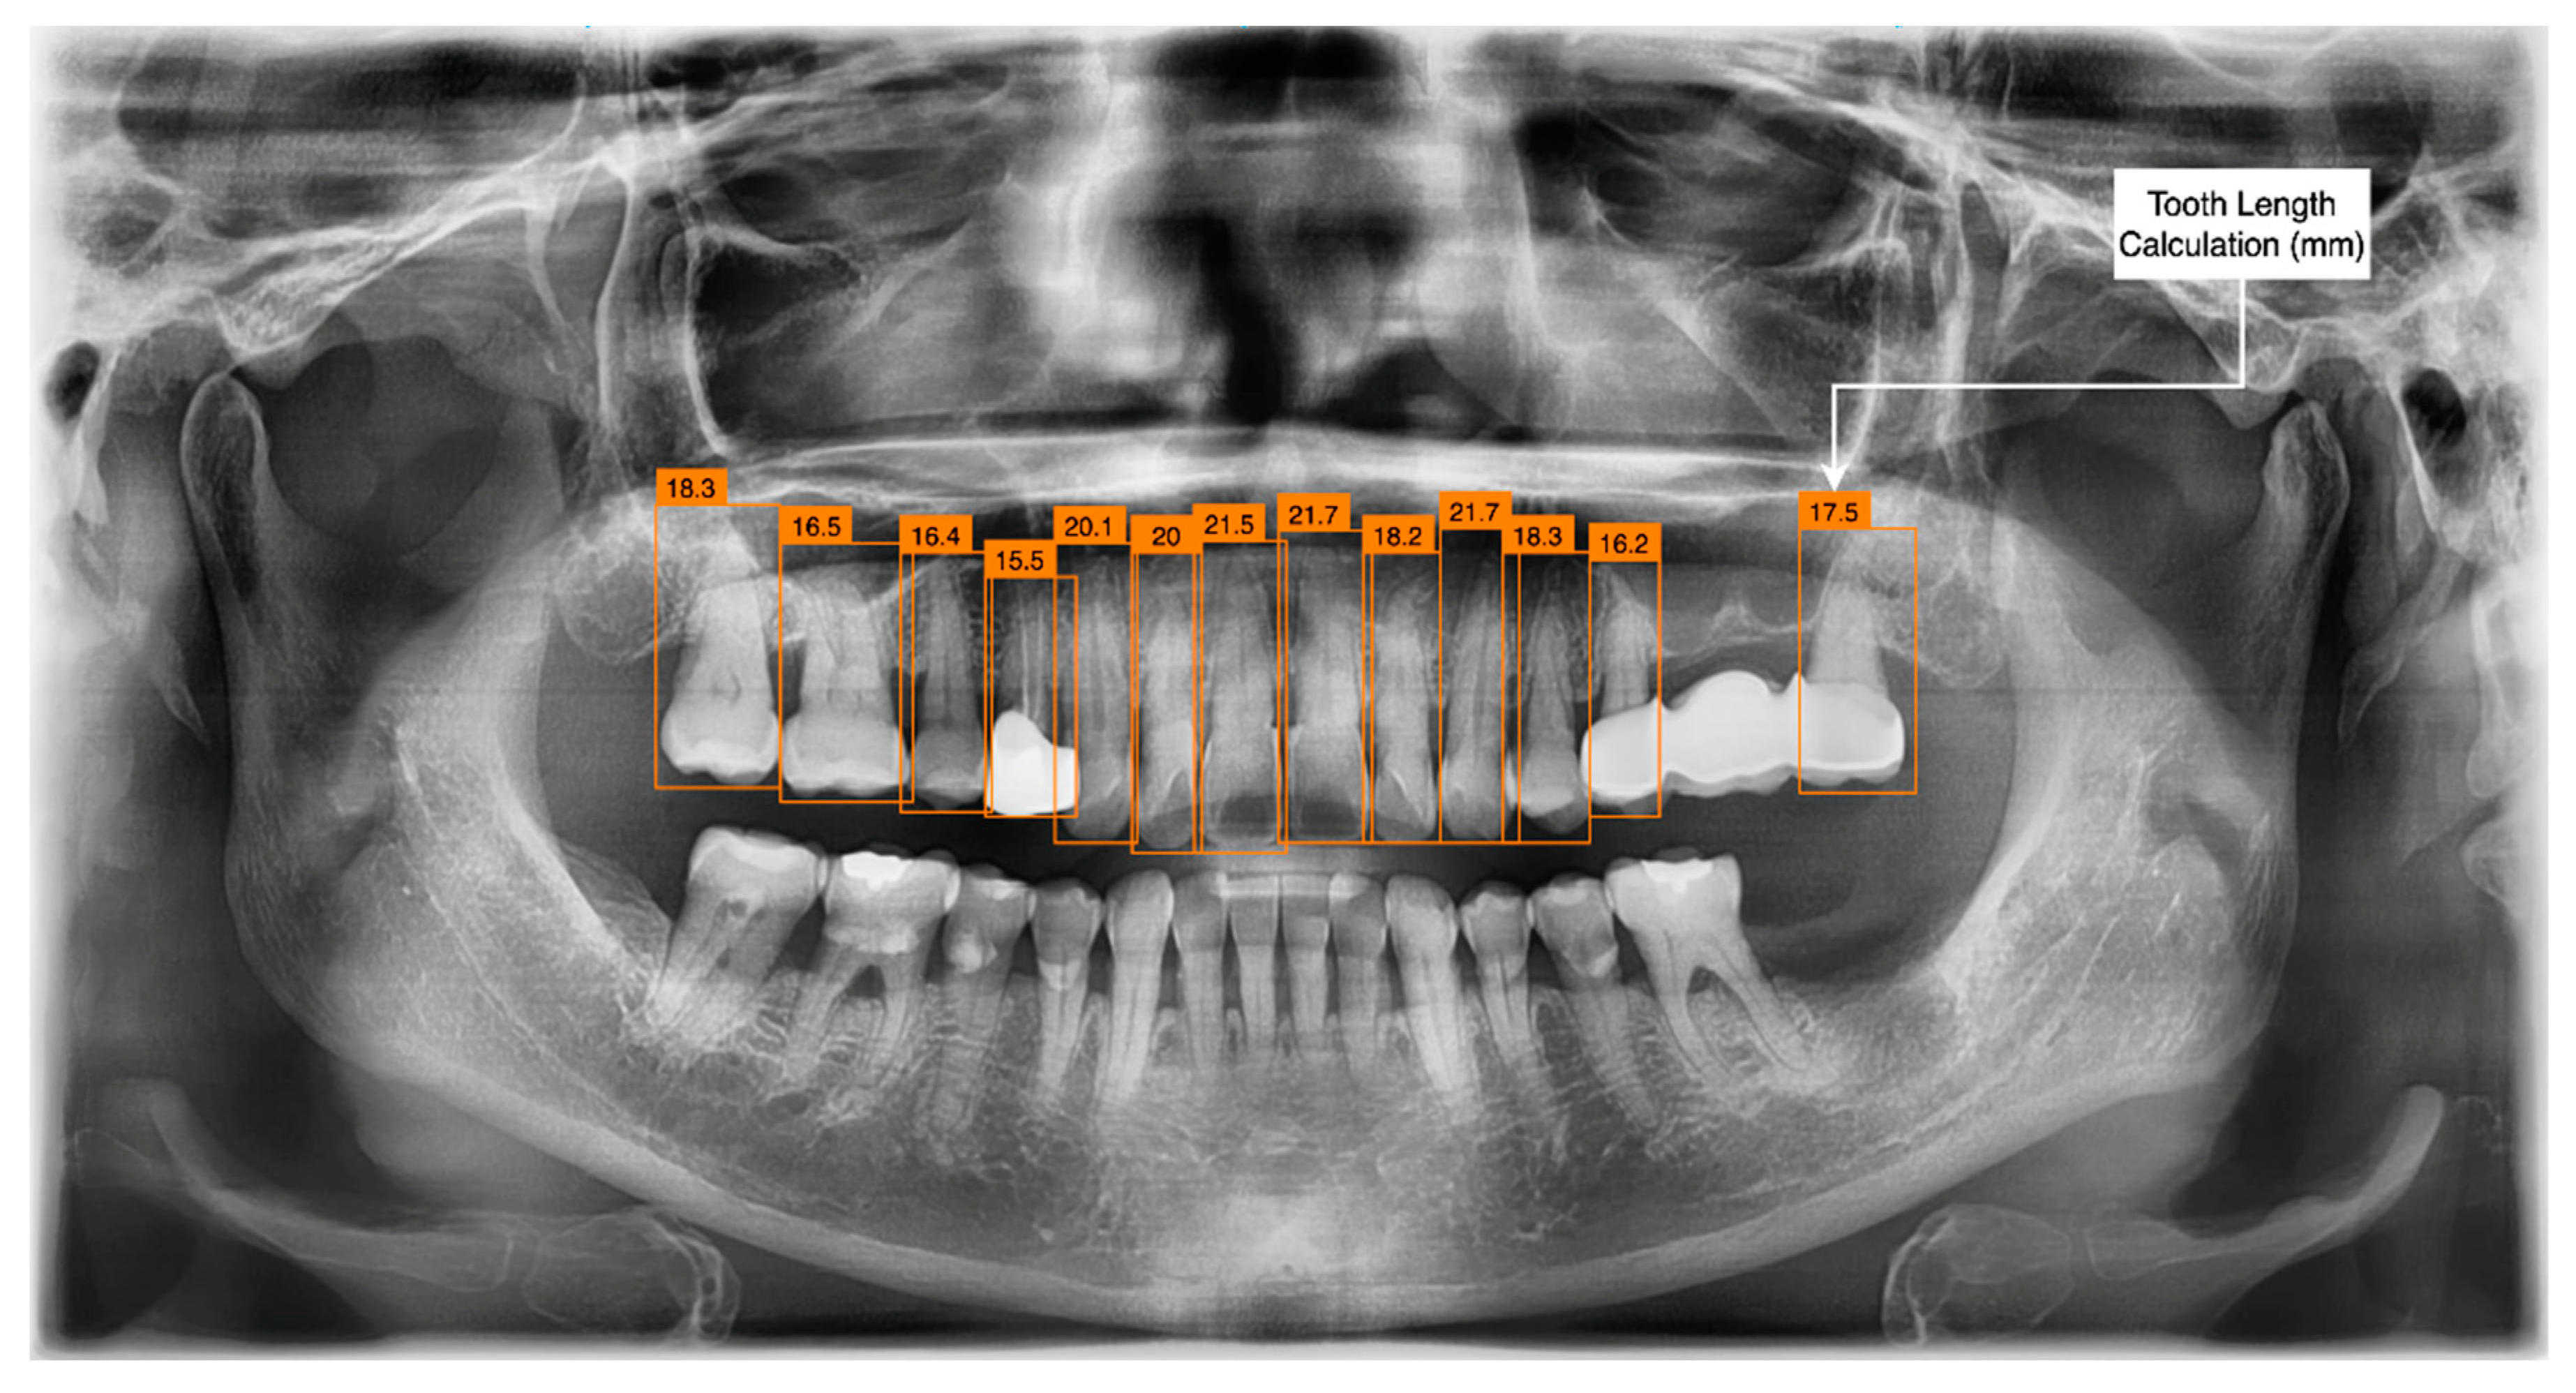

3.3. Tooth Identification through YOLOv5

3.4. Determination of Tooth Stage through U-Net and YOLOv5 Integration